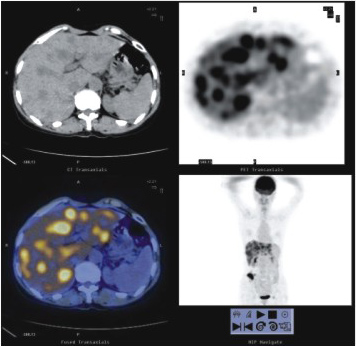

2、 良、惡性鑒別及尋找原發(fā)灶和轉(zhuǎn)移灶

PET-CT顯像作為功能顯像,能夠揭示機(jī)體細(xì)胞代謝的異常變化,因而能較容易鑒別腫瘤是良性還是惡性;而PET-CT顯像能同時(shí)獲得PET與CT兩者的全身的斷層圖像,對于腫瘤原發(fā)灶與轉(zhuǎn)移灶的診斷尤為有利。

肺癌合并炎癥及遠(yuǎn)端肺不張 | 胃癌多發(fā)肝轉(zhuǎn)移 |